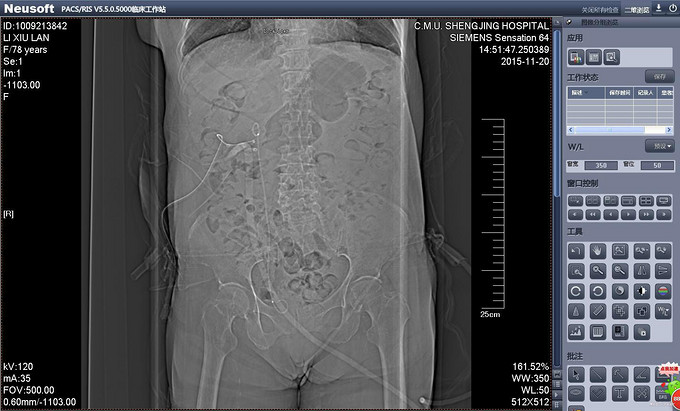

辅助检查:PCNL术后出院前复查CT提示双J管位置位于膀胱内。(图术后复查CT 1、2) 输尿管镜拔管前再次复查CT提示双J管缩回输尿管内(缩回后CT1、2)